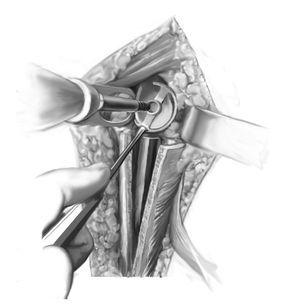

Figuras 3a a 3e. Exposición del húmero proximal y preparación para la ventana ósea. Se abre una ventana ósea pediculada al pectoral mayor con una sierra oscilante y se abre en sentido medial (a-c). Se libera la prótesis cuidadosamente utilizando escoplos pequeños y se saca (d, e). La planificación de la ventana ósea y del pectoral mayor tiene en cuenta los siguientes factores: preservación de la inserción del músculo deltoides, la longitud mÃnima requerida de la ventana para extraer la prótesis y el tapón distal de cemento, y conservación de una longitud suficiente de anclaje distal humeral. Se moviliza medialmente la ventana humeral pediculada. Se va aflojando el cemento trozo a trozo y se va extrayendo hasta que se pueda sacar toda la prótesis. Deberá extraerse cualquier trozo de cemento que quede sobre el hueso, con ayuda de la fresa de alta frecuencia, especialmente si está adherido a fragmentos corticales muy finos. También se puede usar la fresa para avanzar distalmente en el tapón de cemento remanente. Se pasa una cinta deslizante por debajo de la inserción del pectoral mayor (flecha en los bordes proximal y distal, b), cerca del húmero proximal. Si hay cemento residual en la región diafisaria por debajo de la ventana ósea, se puede abrir la diáfisis con una broca o con un extractor de ultrasonidos y se puede ensanchar progresivamente de manera que se pueda extraer el cemento con un pequeño gancho.

Figuras 4a a 4c. Extracción del tapón residual de cemento. Si el tapón de cemento continúa distal a la punta de la prótesis, se debe ensanchar la zona mediante fresas de tamaño creciente y se extrae poco a poco con pequeños ganchos (a-c). Si el tapón de cemento se extiende muy lejos distalmente y se adhiere muy firmemente a la cortical ósea fina y osteoporótica, se pueden realizar dos procedimientos: 1. Extensión de la incisión cutánea distalmente, exposición del nervio radial y ampliación de la ventana ósea; 2. Fresado del tapón de cemento como mÃnimo hasta los 8 mm y colocación de componente vástago de 6 mm en el tapón de cemento remanente. Para crear un buen anclaje para el implante, se amplÃa cuidadosamente la diáfisis humeral utilizando fresas de diámetro creciente hasta que se haya alcanzado la cortical distalmente. Tras el fresado, se determina la longitud del implante. En una situación de revisión, suele ser necesario utilizar vástagos de 150-210 mm de longitud. En general, la continuidad de la metáfisis humeral está con frecuencia interrumpida, de manera que no es necesario disecar más como en las cirugÃas primarias. En estos casos, es especialmente importante recuperar la altura humeral para lograr una retroversión correcta de la prótesis. Se debe lograr un balance entre, por un lado, lograr un cierre con estabilidad suficiente (al menos 20º de retrovesión con respecto al eje longitudinal del antebrazo, que corresponde aproximadamente a unos 10º de retroversión anatómica), el choque con el reborde glenoideo antero (inferior y postero/superior en los extremos de las rotaciones) y por otro lado, las necesidades funcionales del paciente (más rotación interna a expensas de rotación externa cuando hay daño añadido de las articulaciones adyacentes, p. e., artritis reumatoide). En caso de duda, cuando hay riesgo de luxación debido a contracturas o defectos musculares, es preferible aumentar la retroversión; en los casos en que se da prioridad a la rotación interna, es mejor colocar la prótesis en posición neutra. Se debe reconstruir tanto como sea posible el húmero proximal utilizando los restos de hueso y de partes blandas. Esto incluye movilizar los restos de las tuberosidades y realizar una fijación circunferencial segura con suturas o con cerclajes alámbricos (de 1,0-1,2 mm). Después de preparar el húmero, se coloca el vástago en la diáfisis sin anclarlo definitivamente, con el fin de proteger el húmero restante durante la siguiente disección. Se colocan los alambres de cerclaje, o como alternativa, suturas de Fiber-wire alrededor del húmero proximal preparados para la fijación posterior de la ventana humeral.